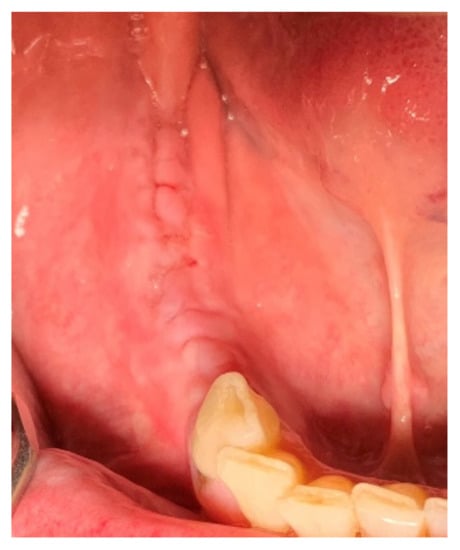

The 66-year-old patient was a healthy non-smoking female patient who lost her right mandibular molars for a long time. Previous implant placement was not successful, and an implant failure was present due to an implant fracture. Due to the risk of damaging the mandibular nerve, the broken implant was left in the jaw (as a “sleeping” implant), covered completely by the bone. That implant was left in the jaw, which presented a severe atrophy, with a remaining residual bone height of approximately 4 mm. Based on the height, the placement of short implants was not an option, and the patient was informed about the different grafting options, as well as the possible intraoperative and postoperative complications (Figure 1).

Figure 1.

Clinical situation: bone deficiency in the right posterior mandible.